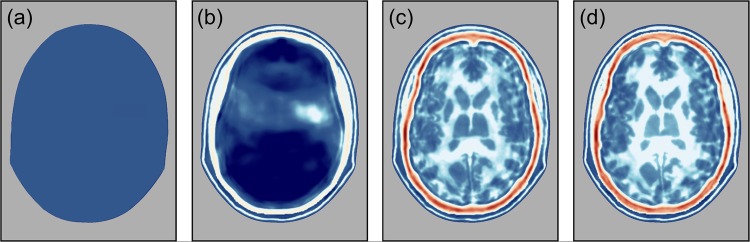

Figure 4b shows the failure of an attempt to recover a model of the head using conventional FWI beginning from the purely homogeneous starting model shown in Fig. 4a. This should be compared with Fig. 3g, which shows the analogous result obtained when the starting model contains an accurate model of the skull. The reason for the failure of this attempt is that conventional FWI will not converge to the correct global solution if inversion begins from a model that is too far removed from the true model. Specifically, for successful FWI, the data generated by the starting model must not be shifted in time by more than half a wave cycle at the lowest frequencies that are present in the data. When that condition is not met, the data are “cycle skipped”, and FWI will then typically fail.

Fig. 4. Inverting from a homogeneous starting model.

a Homogeneous starting model with velocity of water. b Model recovered using conventional FWI. c Model recovered using AWI. d Model recovered by FWI following AWI. The colour scale is as shown in Fig. 3. Note that the skull is not present in the starting model, and the final model is well recovered.

AWI is a modification of FWI that is less sensitive to the quality of the starting model, and it is able to move towards the true model even when the data are cycle skipped. It does, however, pay a price for this robustness, and the models that it is able to produce on its own are not normally as well resolved as those that can be produced by FWI. The solution then is to begin with AWI from a simple homogeneous cycle-skipped model, then switch to conventional FWI once AWI has moved the model sufficiently far towards the true model that they are no longer cycle skipped19.

Figure 4c shows the result of applying AWI, using the same data and starting from the same homogeneous model as was used to generate Fig. 4b. Now the attempt to recover a model of both the skull and the brain has been reasonably successful, and no a priori model of the skull has been assumed. The AWI model though is not the final result. Figure 4d shows the results subsequently obtained by conventional FWI beginning from a smoothed version of the model previously recovered by AWI. The final model recovered by this combination of methods is now accurate and compares well to the model in Fig. 3g that was recovered using a perfect model of the skull. AWI and FWI together then can fully solve the problem of building a well-resolved accurate model of skull and brain purely from ultrasound data without any a priori knowledge of the skull.